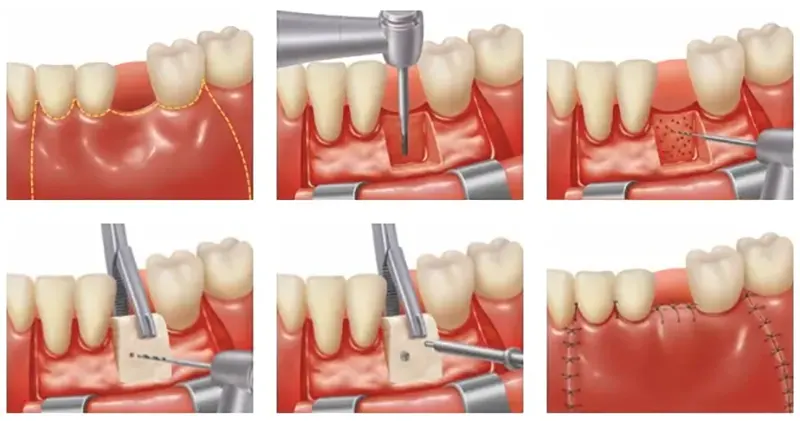

Exposure of Impacted Canine Surgery

An impacted tooth means the tooth is stuck and cannot erupt into function. The maxillary canine (cuspid or upper eyetooth) is the second most common tooth to become impacted. Early recognition of impacted canines is the key to successful treatment.

Impacted canine exposure is a minor oral surgical procedure that exposes the stuck (impacted) canine. Overlying gum tissue and bone will be removed, followed by bonding an orthodontic bracket and a gold chain to the impacted canine. Orthodontic treatment will slowly guide the tooth into its proper position. It is crucial for treating teeth that fail to erupt, preventing overcrowding, damage to neighboring tooth roots, and, in rare cases, cyst formation.